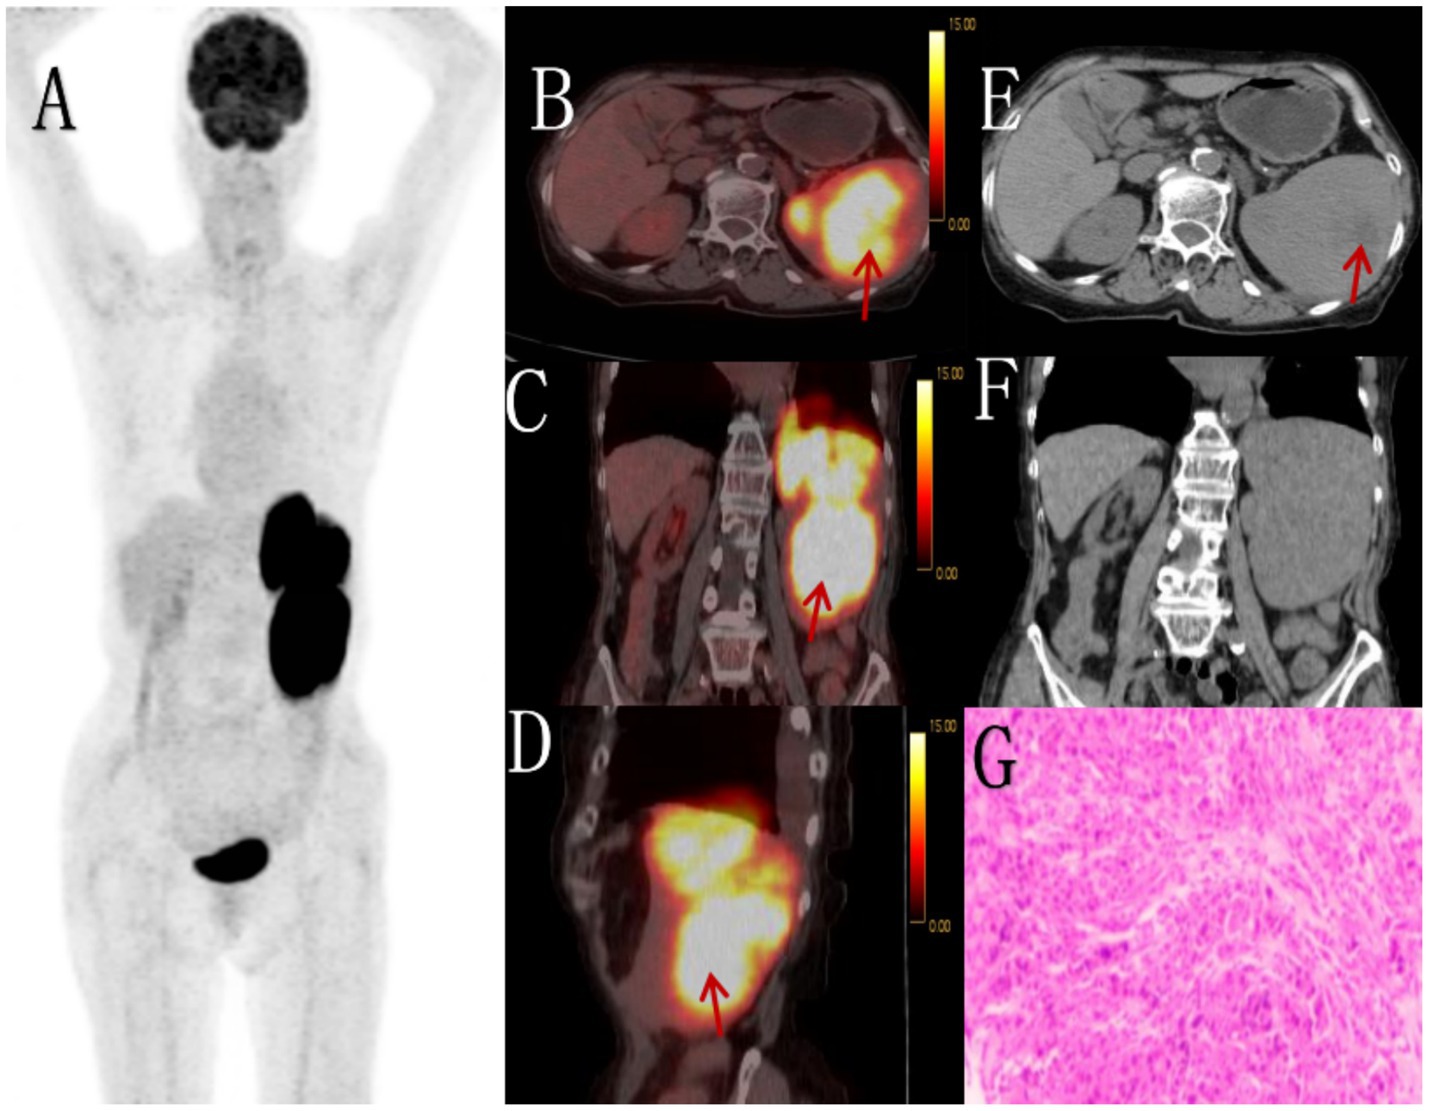

Figure 3

Female, 68 years old, EBV + IFDCS. (A) whole body MIP, (B) enhanced CT-arterial phasel, (C) enhanced CT-venous phase, (D) axial fusion, (E) H-E × 400, (F) Immunohistochemistry CD35, +, (G) EBER-by in-situ hybridization, +. 18F-FDGPET/CT showed circular low-density shadows in the spleen with clear boundaries, uneven internal density and low-density necrosis. FDG metabolism was significantly increased, showing uneven clumps of increased FDG metabolism, SUVmax was 7.8 (arrow, D). Non-contrast CT showed an enlarged spleen volume, a quasi-circular low-density mass with clear boundaries and necrosis in the spleen. Enhanced CT showed uneven delayed enhancement of the solid part, mild to moderate enhancement of the tumor in arterial stage, progressive enhancement in venous stage and delayed stage (arrow, C), no enhancement of necrosis, and mild pseudoenvelope enhancement (arrow, B). The tumor cells appeared oval and were arranged in bundles, nodules or small nests. The cytoplasm was eosinophilic, lightly stained, and the nuclear chromatin was fine, with small nucleolus and no mitotic image (E).